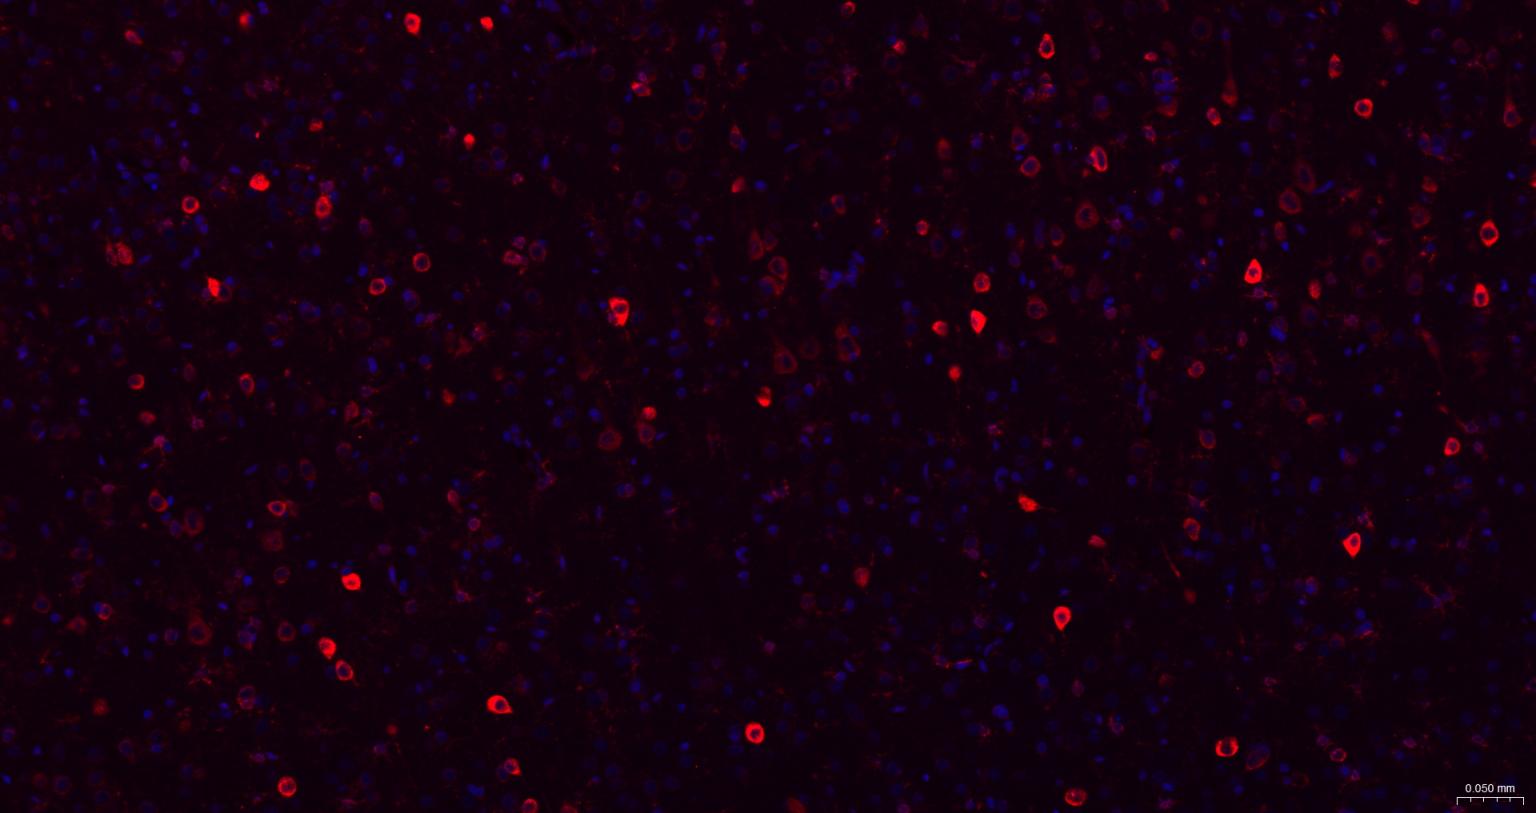

Paraformaldehyde-fixed, paraffin embedded Mouse Cerebrum; Antigen retrieval by boiling in sodium citrate buffer (pH6.0) for 15 min; The section was incubated with MSI2 Monoclonal Antibody, Unconjugated (bsm-61244R) at 1:200 overnight at 4°C. Followed by conjugated Goat Anti-Rabbit IgG antibody (Red, bs-0295G-BF594), DAPI (blue, C02-04002) was used to stain the cell nuclei.

Paraformaldehyde-fixed, paraffin embedded Rat Cerebrum; Antigen retrieval by boiling in sodium citrate buffer (pH6.0) for 15 min; The section was incubated with MSI2 Monoclonal Antibody, Unconjugated (bsm-61244R) at 1:200 overnight at 4°C. Followed by conjugated Goat Anti-Rabbit IgG antibody (Red, bs-0295G-BF594), DAPI (blue, C02-04002) was used to stain the cell nuclei.